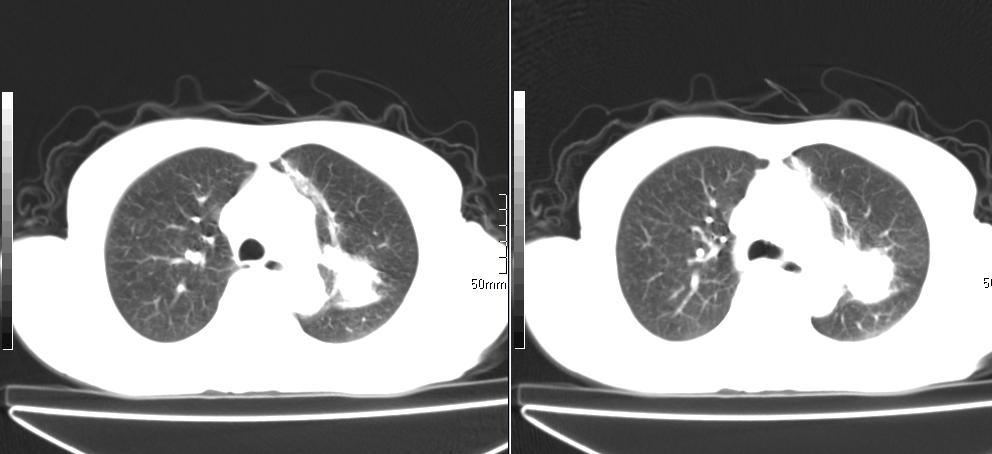

标题: CT26857:女,60岁,胃部不适前来就诊,不咳嗽,乏力,胸椎 [打印本页]

1、胸椎有骨质破坏伴周软组织,考虑胸椎转移。2、考虑左肺上叶尖后段支气管开口区周围型肺癌可能。

中央肺癌

1、胸椎有骨质破坏伴周软组织,考虑胸椎转移。2、考虑左肺上叶尖后段支气管开口区周围型肺癌可能。建议行纤支镜检查!

1、胸椎有骨质破坏伴周软组织,考虑胸椎转移。2、考虑左肺中央型肺癌可能。